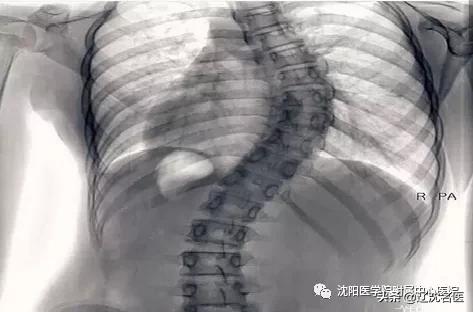

青少年特发性脊柱侧弯是指脊柱向侧方偏移10度以上的脊柱三维畸形,是一种非常常见,却有致残性的畸形。该病发病隐匿,多在10-15岁发病,男女比例1:7。这个时期的青少年,正值青春期,并处于学业负担加重时期,还有部分学生住校,家长很难及时发现孩子体态的改变。

如果由于早期没有得到关注而延误诊治,使脊柱侧弯度数>40度时,则极易发生不可逆的加重,而只能考虑手术治疗。这不仅影响了孩子的身心健康,更是增加了治疗的风险和家庭及社会的经济负担。

早治疗:脊柱侧弯一旦确诊,应及时与治疗者配合,进行矫正体操训练,且逐渐增加每天的运动康复训练强度。当脊柱侧弯度数>45度,并严重影响了孩子的心肺功能及身心健康,则考虑手术治疗,同时术前术后也要进行运动康复,更好的恢复脊柱功能。